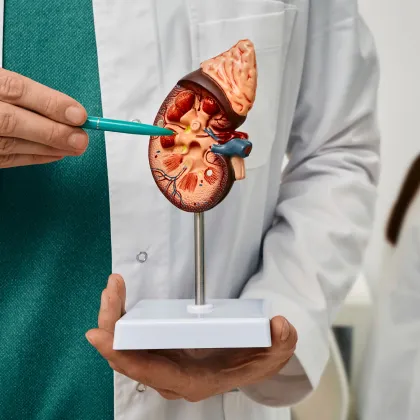

- 요로결석

1:1 맞춤 수술을 위한

다양한 사전정밀검사 시스템

X-ray

비뇨기에 양성 또는 악성으로

덩어리가 생긴 경우

요관내시경

(경성/연성)

요관으로 삽입하여 홀뮴레이저로

결석을 파쇄하는 무절개 내시경 수술

요로결석

- CT검사(원외검사)

- X-ray

- 초음파

- 체외충격파쇄석술

- 요관경 레이저 결석 제거술

- 홀뮴 레이저 수술